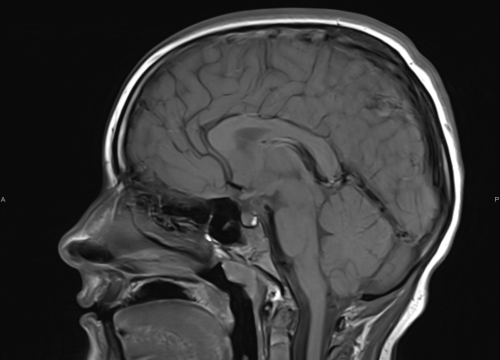

FOTO Ako su vam potrebni specijalistički pregledi mamografija, RTG, UZV, CT i MR, koji se inače koriste za dijagnostiku velikog broja zdravstvenih problema, možete ih obaviti već danas ili sutra. Vodite računa o vašem zdravlju i zakažite pregled u Poliklinici Affidea Vita u Šibeniku na vrijeme!